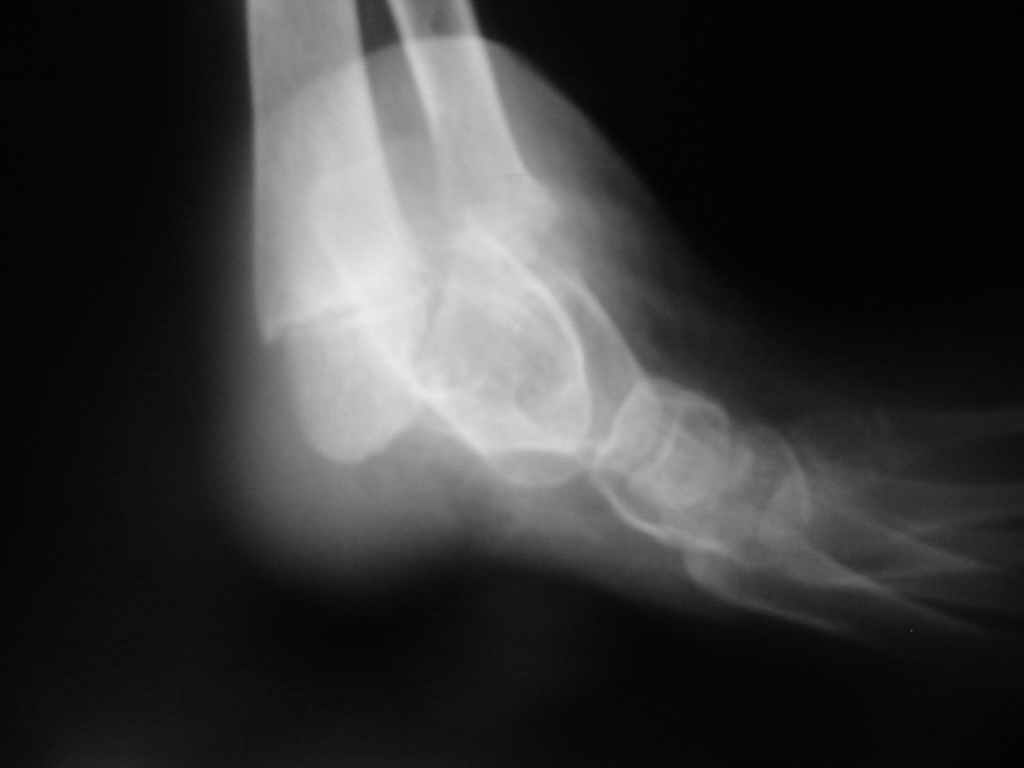

Судя по представленным фото и Рг граммам, у 13 летнего ребенка врождённая гемимелия большеберцовой кости, таранно-пяточный синостоз Из-за отставания в росте большеберцовой кости (остутствует дистальный эпифиз с зоной роста) произошла компенсаторная гиперофия малоберцовой кости, на которую приходится основная нагрузка (спонтанная тибиализация малоберцовой кости). Как результат дисбаланса осевого роста вторично возникла эквино-варусная деформация стопы. Продолжающийся рост ребёнка (до естественного закрытия зон роста) будет приводить к усугублению деформации по приведенным выше причинам.

Поднадкостничную остеотомию большеберцовой кости в средней трети с формированием синостоза с малоберцовой ( активно растущей) костью и второй уровень в области дистального тиб/фиб синдесмоза- достигается баланс роста( средне-медиальный и латеральный отделы) в области измененного голеностопного сустава. Коррекция эквино-варусной деформации стопы в аппарате после чрезкожной сегментарной тенотомии ахилова сухожилия. Дело

кропотливое и длительное.

Как резервный вариант может быть рассмотрена ампутация в верхней трети голени с изготовлением функционального протеза, если родители ребенка не настроены на длительную коррекцию и многоэтапную хирургию, родственники должны понимать, что абсолютного функционального результата даже после этапных операций достичь будет невозможно (аномальный голеностопный сустав, таранно-пяточный синостоз).